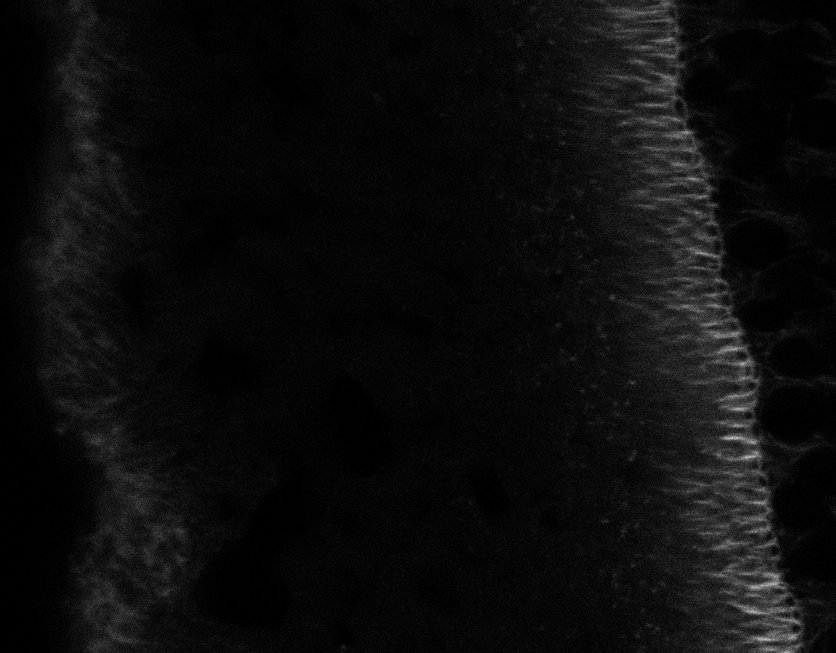

Healthy Choroid

Unhealthy Choroid